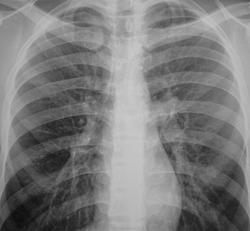

Формально фтизиатры поставят диагноз инфильтративный туберкулез S6 правого легкого, фаза распада. Но, я не зря спросил про возраст больного. У молодых людей нижнедолевой туберкулез особенно в 6 сегменте часто связан с поражением внутригрудных лимфатических узлов. Пути распространения инфекции лимфобронхогенное. Подтверждением этого является обнаружение при бронхоскопии различных форм активного туберкулеза (инфильтративный, язвенный и лимфобронхиальный свищ). При бронхоскопии у больного могут найдут специфическое поржение бронхов. Лимфогенный путь распространения напоминает раковый лимфангиит . О лимфогенном распространении инфекции указывает прединфильтратная сетка, которую хорошо видно на рентгенограммах. О поражении лимфатических бронхопульмональных узлов свидетельствует вовлечение в процесс плевральных листков в виде воспалительного уплотнения междолевой плевры, а также наклонность к раннему образованию распада. Известно,что у взрослых трудно выявить изменения со стороны ВГЛУ, так как они не часто достигают той величины, как у детей. Умеренно выраженное увеличение бронхопульмональных л/у на КТ диагностируется только при контрастировании. Таким образом, предварительный патогенетический диагноз звучал бы так : туберкулез внутригрудных лимфатических узлов бронхопульмональной группы справа, осложненный бронхолегочным поражением в S6 с распадом. Необходимо построить патогенетический диагноз, так как специфические изменения в лимфатических узлах требуют более длительного лечения. Такова моя точка зрения на диагноз у представленного пациента. С уважением Ваш NIkolas